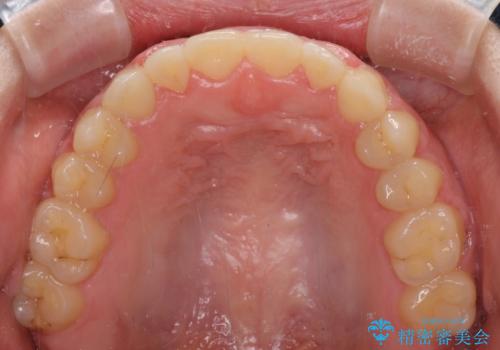

上顎骨を拡大したことで、下顎の歯列を上顎が受け入れられるようになりましたが、インビザラインでは咬み合わせを改善させることができなかったため、ワイヤー矯正にて仕上げることとしました。

ワイヤーを使用したものの、上下前歯のオープンバイトがなかなか改善されませんでしたが、患者希望により治療終了となりました。